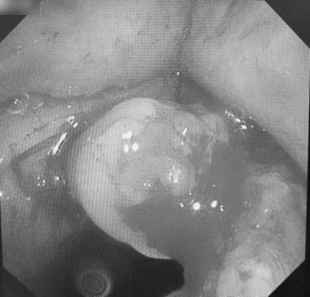

经过充分讨论后,决定为患者在全麻、气管插管下,采用经气管镜下介入方法完成局部手术切除治疗。

之后,西安高新医院呼吸与危重症医学科王丽峰副主任在呼吸内镜室严密生命体征监测及呼吸机支持条件下,在气管插管后进入电子支气管镜,针对右侧声带肿物准确快速清除,并局部创面的冻融治疗。整个操作过程时间短、出血少,患者苏醒快,氧合及生命体征稳定。